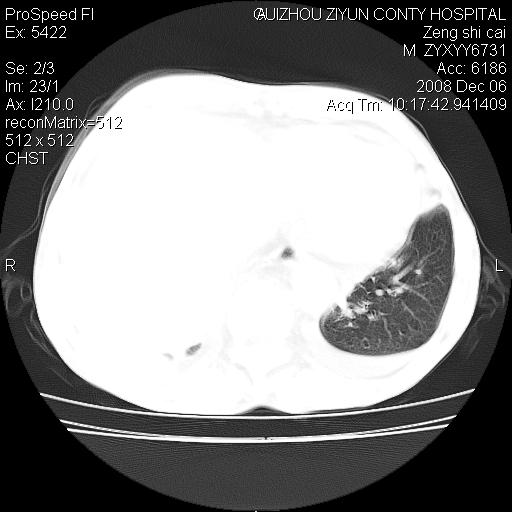

标题: CT16961:M、71岁,咳嗽半年,无血痰;胸片示右肺占位。 [打印本页]

标题: CT16961:M、71岁,咳嗽半年,无血痰;胸片示右肺占位。

1)考虑右肺上叶纵隔型肺癌伴纵隔淋巴结转移。2)心包积液,双侧胸腔积液。

右肺上叶纵隔型肺癌伴纵隔淋巴结转移。心包积液,双侧胸腔积液。